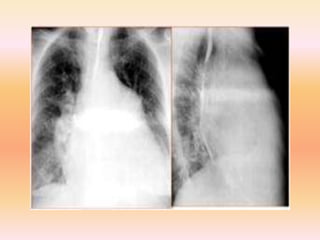

Este documento describe el conducto arterioso persistente, una afección congénita que causa una comunicación anormal entre la arteria pulmonar y la aorta. Afecta a aproximadamente 1 de cada 2,000 recién nacidos y es más común en mujeres. Sin tratamiento, puede causar insuficiencia cardíaca y otros problemas de salud graves. El tratamiento incluye el uso de indometacina para cerrar quirúrgicamente el conducto o dispositivos de oclusión como coils y amplatzers que se colocan mediante cateterismo.